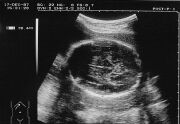

BPD kesiti

Yandaki ultrason resminde bebeğinizin kaş ve şakak seviyesinden alınmış bir kafatası kesitini görüyorsunuz. BPD (Biparietal Diameter) adı verilen bu kesit bize beyin içi yapıları incelememize ve kafatasının haftasına uygun gelişip gelişmediğini değerlendirmemize olanak verir.